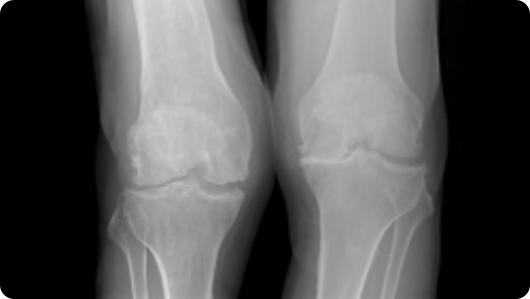

Radiographic image of knee arthritis Radiographic image of a total knee replacement

Knee Arthritis

Total Knee Replacement